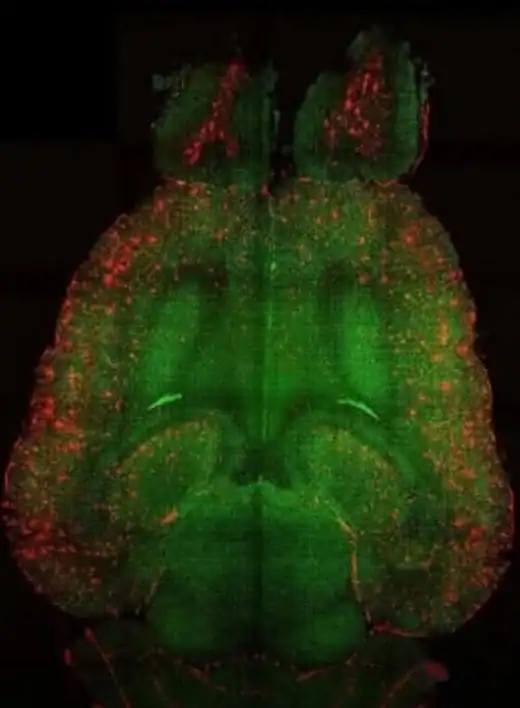

Pesquisadores anunciaram um avanço considerado promissor no combate ao Doença de Alzheimer. Estudos experimentais conseguiram remover placas beta-amiloides do cérebro, estruturas tóxicas associadas à progressão da doença.

Essas placas se acumulam entre os neurônios e prejudicam a comunicação entre as células cerebrais. O processo está relacionado a sintomas como perda de memória, confusão mental e declínio cognitivo.

Nos experimentos, cientistas observaram que a remoção dessas estruturas levou a melhora em sinais neurológicos e a uma recuperação parcial da atividade cerebral nos modelos analisados.